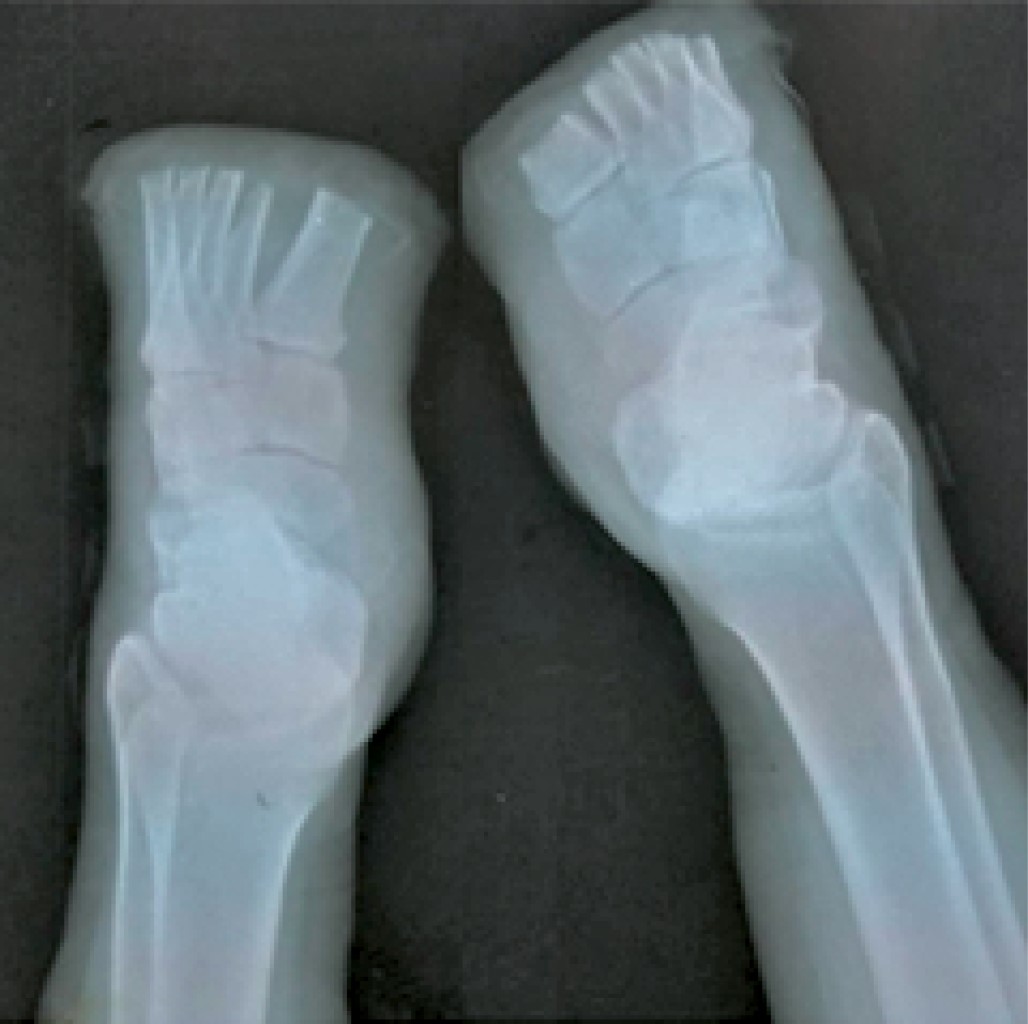

Paciente masculino de 45 años, quien sufre aplastamiento de ambos pies con pieza metálica de una tonelada durante dos minutos. A su ingreso a urgencias se realiza radiografía anteroposterior y oblicua de ambos pies, donde se encontró: pie derecho con fractura subcapital de primer metatarsiano + fractura diafisaria de segunda y tercera falange proximal + fractura de cuarta y quinta falange distal y pie izquierdo con fractura de primer falange proximal + fractura diafisaria de segunda y tercera falange proximal + fractura de cuarta y quinta falange distal, por lo que se concluye el diagnóstico de pie traumático bilateral. Clínicamente se encontró con palidez en dedos de pies, disminución de pulso pedio (de tres a cuatro segundos), y disminución de la temperatura, además se hizo ultrasonido Doppler concluyente de lesión de arteria pedia. Ese mismo día de la lesión se realiza aseo, cirugía más amputación de quinto dedo pie izquierdo. Se decide limitar la necrosis durante 10 días (Figuras 1 y 2).

Figura 1

Figura 2